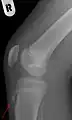

![]() Radiografía lateral de la rodilla demostrando fragmentación del tubérculo tibial, con tejido sobreabundante | ||

Una radiografía de hueso puede ser normal o puede mostrar inflamación o daño a la espina tibial. Las radiografías se usan muy poco, a menos que el médico quiera descartar otras causas del dolor.

Rayos X mostrando la enfermedad de Osgood-Schlatter